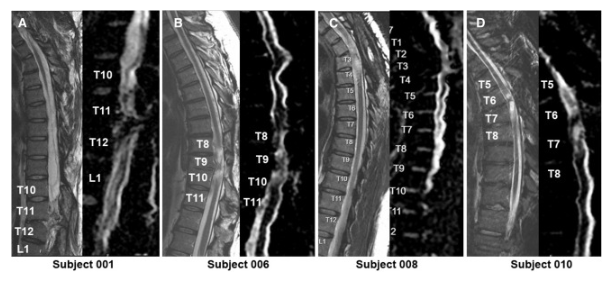

通過 MRI 和 DTI 成像評估動態反應

在 NSC 注射后,沒有放射學證據表明出現即時或延遲并發癥,包括術后即時或隨訪成像中沒有出現新的脊髓或軟組織水腫區域、增強或腫脹或積液。在純解剖或擴散張量序列中均未觀察到脊髓脊髓軟化癥的可見形態變化。

在所有四名患者中,彌散張量成像 (DTI) 成像顯示在損傷部位和損傷部位的前端/尾部脊髓束外觀穩定,但未顯示重塑或纖維束造影改善的廣泛證據。

體格檢查顯示兩名患者的神經損傷水平 (NLI)、運動評分和感覺評分均有所改善。與細胞移植兩年后的神經系統評分相比,5 名受試者 001 的改善水平從兩年時的 2 個水平(改善)下降到五年時的?? 1 個水平。受試者 010 的改善在兩年和五年時均保持穩定在 1 個水平的神經系統改善。